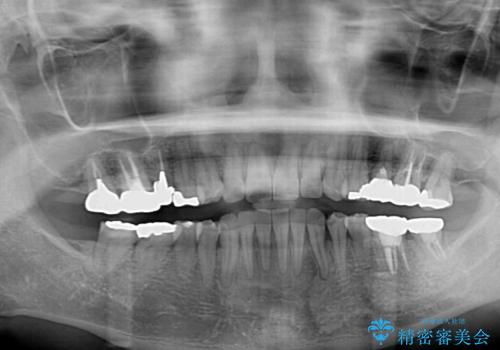

矯正治療後のレントゲン写真では、根尖部に認められた病変(骨の溶けていた像)は消失していることが分かりました。